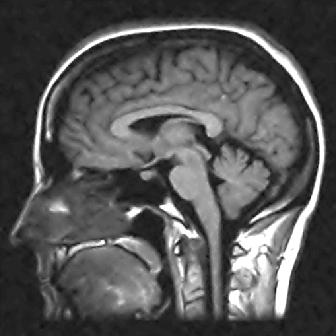

We display the ground truth image and the reconstructed images from the inverse Fourier method, the PCM-TV method and the PCM-TV-TFV method in Fig. 10.

Refer to caption

(a) Ground Truth

(b) Noisy

(c) PCM-TV

(d) PCM-TV-TFV

Figure 10: Reconstruction comparison between PCM-TV and PCM-TV-TFV. Noisy image (b) is obtained from inverse Fourier transform. Here m=128×128𝑚128128m=128\times 128, n=96×96𝑛9696n=96\times 96, imsize=256×256𝑖𝑚𝑠𝑖𝑧𝑒256256imsize=256\times 256, σ=0.4𝜎0.4\sigma=0.4.

We point out that the noisy image in Fig. 10 is obtained directly by inverse Fourier transform and we can see that the noise level is quite high in this case. Both the PCM-TV and the PCM-TV-TFV are able to produce more reasonable visual results. To see a deep comparison, we zoom in the red square part of Fig. 10 and present the approximation errors in Fig. 11.